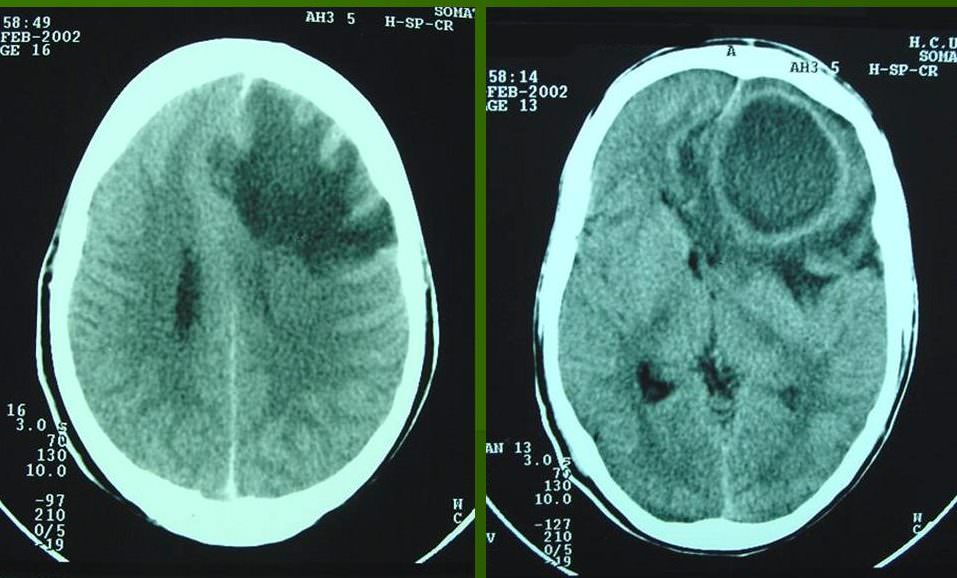

- 1 стадия (1-3 дня) наблюдается энцефалит – это начальное воспаление мозга. Самый легкий период, болезнь поддается излечению благодаря антибактериальной терапии или проходит самостоятельно путем рубцевания.

- 2 стадия (4-9 дней). В абсцессе уже образовался гнойник, который с каждым днем увеличивается в объёмах, если не обращаться к медикам.

- 3 стадия (10-13 дней). Вокруг гнойной полости образуется защитная пленка, которая не дает образованию распространяться дальше.

- 4 стадия (3 неделя). Пленка полноценно уплотнилась. В некоторых случаях начинается регресс болезни или вокруг капсулы образовываются новые очаги заражения.

Дальше это только подготовка к хирургическому вмешательству. Врачи клиник на данный момент практикуют полное удаление абсцесса или его дренирование. Пунктуационная аспирация применяется на ранних стадиях или на этапе церебрита.

Её эффективность доказана в случаях, когда гнойник расположен глубоко в голове. Если неврология больного покажет наличие воздуха в абсцессе или ухудшение общего состояния пациента – новообразование нужно удалять.